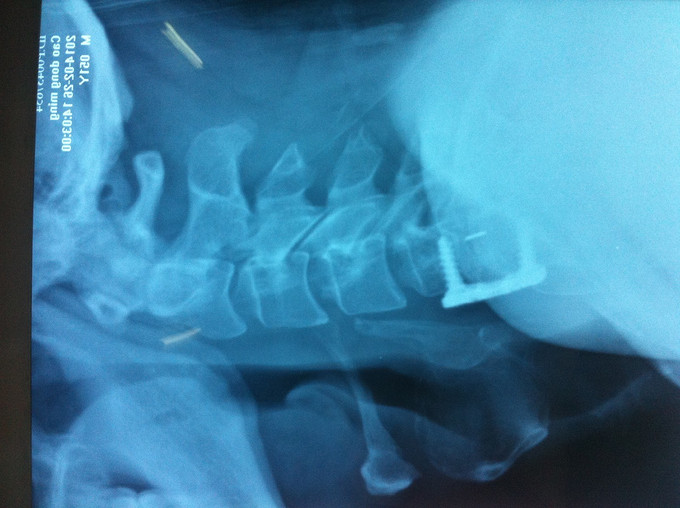

查体:颈后部压痛,颈部活动受限,双侧前臂及手感觉减退,双侧伸腕、伸肘肌肌力4级,双侧霍夫曼综合征阴性,双下肢感觉无减退,双下肢肌张力高,巴氏征可疑阳性,辅助检查: X-ray:劲椎退行性变 CT:颈椎间盘突出,腰5/6 MR:颈椎间盘突出,颈5/6节段明显

诊断:混合型颈椎病 处理: 1、完善相关辅助检查,明确诊断,有无手术指证; 2、完善手术评估,有无手术禁忌,手术风险及并发症; 3、在全麻下行颈椎前路减压,颈5/6椎间Cage植骨融合内固定术